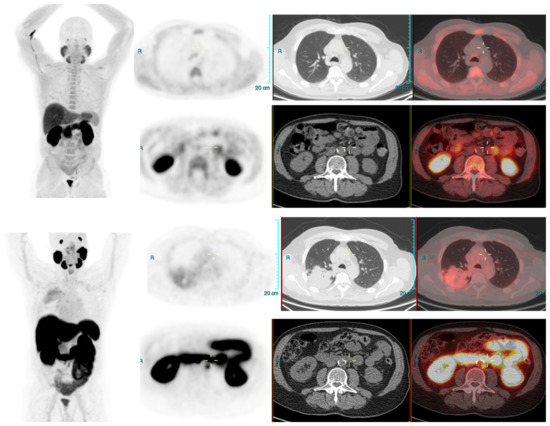

We conducted a separate subgroup analysis of 61 patients (Table 4) who had repeat imaging. Thirty had indeterminate findings on initial PSMA PET CT and the findings changed to a positive lesion in 14 (10 with known small indeterminate pelvic lymph node and four with known indeterminate prostate focus, PSA increase of 0.7 to 3.0 in 6 months), negative in eight (four with pelvic lymph node, four with uptake in bones on prior PET CT, PSA increase of 0.13–2). Six patient had the same indeterminate small pelvic lymph node, two had the same indeterminate retroperitoneal lymph node (PSA increase of 0.4 to 2.5). Overall, the follow-up PSMA PET CT was able to conclude in 24/30 patients on follow-up. Of the 31 patients who had repeat PSMA PET CT scans done for a further rise in PSA levels (PSA rise range 0.3–10), 24 had new lesions (prostate lesion in four, prostate and seminal vesicle involvement in four, pelvic/retroperitoneal lymph nodes in 12, new bone lesion in four) and eight had negative scans even on repeat imaging (PSA rise 0.3–2.3). For example, patient in Figure 2 had negative scan at PSA of 3.4 ng/mL, PSA velocity of 1.3 ng/mL in six months. The uptake in right humerus is at the site of known prior humerus fracture and therefore it was categorized as PSMA RADS 1 B (7). Another patient in Figure 3 had and indeterminate lymph node at PSA 6.5 ng/mL, after rise of 3 ng/mL in 2 years, it was categorized as RADS 3A(7). An interesting finding in this case was the consolidation changes in the right upper lobe, which resolved in a follow-up CT performed after 2 months (Figure 4).

Figure 4.

PSA 0.9 ng/mL. Positive lymph node metastasis and suspicious uptake in prostate.